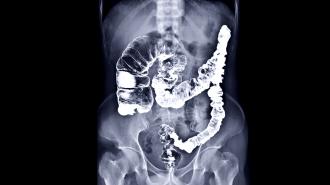

Cancer epigenetics: The team’s two papers, both published in Nature, looked at bowel cancer epigenomes, tracking how they shape the cancer’s growth and evolution towards aggressiveness.

The first study examined 1,373 samples taken from 30 patients with bowel cancer and tracked and characterized their epigenetic changes.